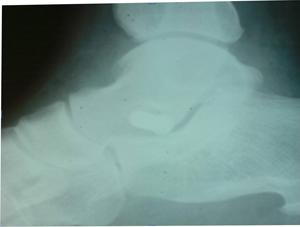

Основным методом диагностики был клинический. Использовались следующие диаг-ностические тесты: пробы с подъемом на носки на одной и обеох ногах (рис.1а,1б), симптом «подглядывающих» пальцев (рис.1в), проба с выявлением гиперпронации. Полученные результаты, позволяют судить о состоянии СЗББМ.

| Рисунок 1. Диагностические тесты: | |

| а - проба с подъемом на носки на одной ноге; б - проба с подъемом на носки обеох ногах; |

в -симптом «подглядывающих» пальцев. |